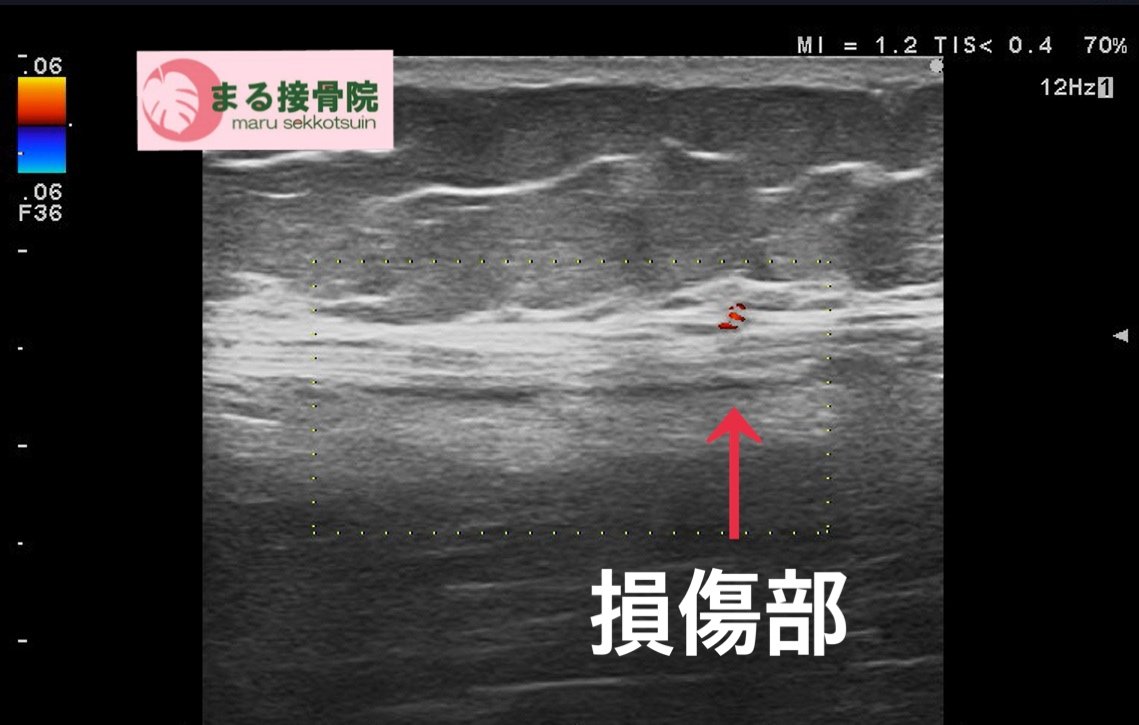

よく問診後、ストレステストを行い、圧痛点を探し、損傷部位確認の為、エコー検査。

結果、半腱様筋部に損傷部位を確認し、軽度ですが「ハムストリングスの肉離れ」と確定。